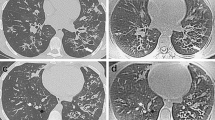

Third, in our study with PROPELLER, MRI tended to overestimate mild CF lung disease and underestimate severe CF lung disease compared to CT. CT appears to have superior sensitivity especially for changes in the periphery of the lung, where small abnormalities, such as bronchiolectasis and mucus plugs can be easily missed by MRI (Fig. 3). To overcome this problem, it is important to further increase the spatial resolution of our routine MRI protocol. This is likely possible with new techniques, such as 3D T1 GRE sequences with radial acquisition in free breathing or in breath-hold condition and highly accelerated parallel imaging [25].

Example of underestimation by chest MRI relative to chest CT. On the left the CT image during inspiration and on the right the correspondent PROPELLER MRI image. Note the peripheral bronchiectasis depicted by CT in the right upper lobe tends to disappear in the correspondent MRI image (white oval). Similarly the small areas of tree in bud in the left lower lobe are blurred and therefore less visible in the correspondent MRI image (white dotted oval)